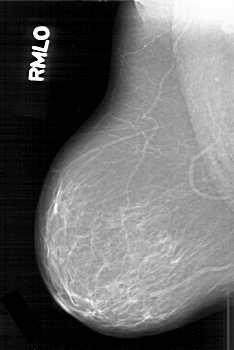

D_4195_1.RIGHT_MLO

RIGHT_MLO LINES 6286 PIXELS_PER_LINE 4201 BITS_PER_PIXEL 12 RESOLUTION 43.5 NON_OVERLAY